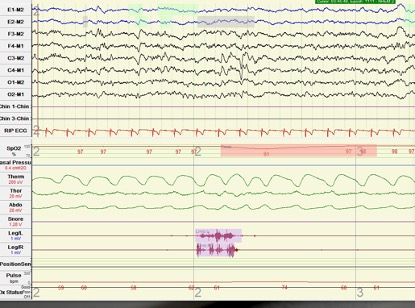

在对张先生进行头颅MRI、甲状腺功能等检查都未发现异常后,长海医院神经内科为张先生进行了睡眠监测,最终找出了原因。神经内科医护人员发现,张先生在睡眠过程中反复出现觉醒(下图红箭头所指空白处),而且微觉醒次数增多。早醒是焦虑患者常见的临床表现之一,因此,神经内科为张先生进行了心理量表的评估。心理量表结果显示,张先生HAMA15分(肯定焦虑)、HAMD14分(无抑郁),被诊断为“焦虑状态”。结合诊断结果,神经内科对张先生进行抗焦虑治疗,经过治疗,他的睡眠和记忆症状都得到明显改善。

与张先生一样,35岁的王女士每晚“睡足”8个小时,但近一年来也反复出现头昏现象,而且多集中在上午时段。在对王女士进行头颅MRI以及头颅CTA检查未发现异常后,长海医院神经内科同样为王女士做了睡眠监测。神经内科医护人员发现,王女士在睡眠过程中频繁出现腿动现象,且腿动之后还会出现微觉醒。经过统计,王女士睡眠中周期性腿动的指数为36次/小时。结合王女士日间功能受损等表现,神经内科将王女士的病症诊断为“周期性肢体运动障碍”。通过指导王女士夜间口服多巴胺受体激动剂后,其夜间下肢不自主运动频次减少,睡眠质量得到改善,头昏症状也明显减轻。

如何才能发现和确立患者睡眠障碍的病因?毕晓莹表示,首先借助的依然还是患者的描述,不过,这种描述往往带有明显的主观色彩;其次,依靠医生的问诊,寻找器质性疾病、情绪障碍、药物等睡眠障碍的诱因;最后,可以借助多导睡眠监测,记录和分析睡眠。通过监测,睡眠会被赋予线条、形状和色彩,成为一副超现实主义的肖像素描,睡眠障碍也就像是一枚枚形态各异“小痣”,跃然纸上,无处遁形。